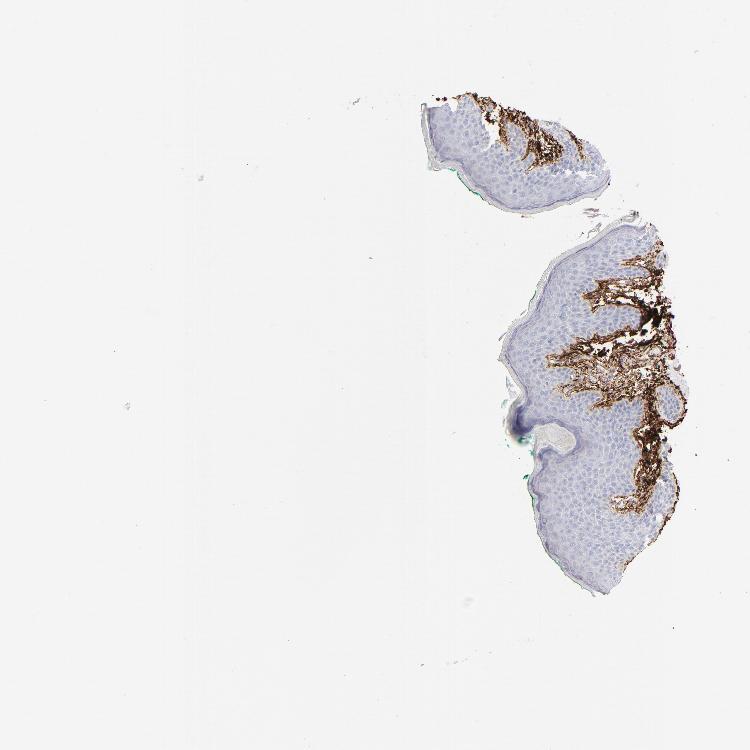

SKIN 2 - Antibody stainingi

Antibody staining in the annotated cell types in the current human tissue is reported as not detected, low, medium, or high, based on conventional immunohistochemistry profiling in selected tissues. This score is based on the combination of the staining intensity and fraction of stained cells.

Each image is clickable and will lead to virtual microscopy that enables deeper exploration of all samples and also displays staining intensity scores, fraction scores and subcellular localization as well as patient and tissue information for each sample.

Antibody HPA001934Antibody CAB018622

Endothelial cells High-

Extracellular matrix High-

Fibrohistiocytic cells High-